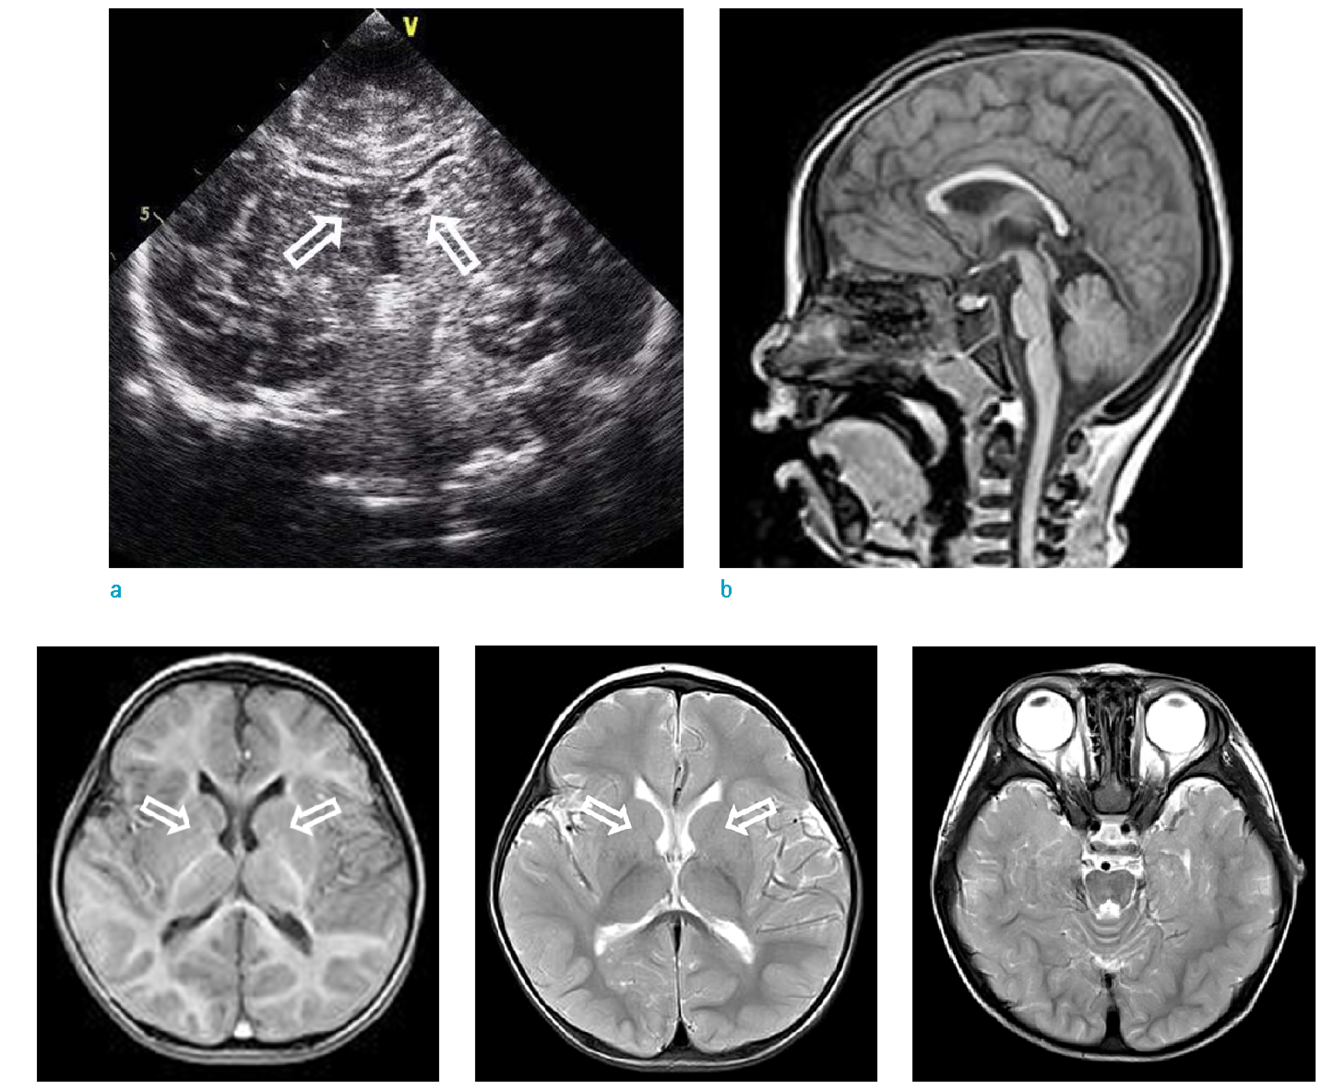

Brain and cerebrovascular malformations are common 6,8:

persistent cavum septi pellucidi and/or cavum vergae (19-33%)

What syndrome is this finding associated with

Di George

CATCH22

C - cavum septum pelucidum, cleft palate,

A - Abnormal Facies (hypertelorism, low set ears, short philtrum, among others)

T - Trunchus ateriosus, Thymic Hypoplasia

C - cardiac anomalies

H - hearing problems. Middle ear malformations. Hypoparathyroidism

22 - Microdeletion of 22q11.2